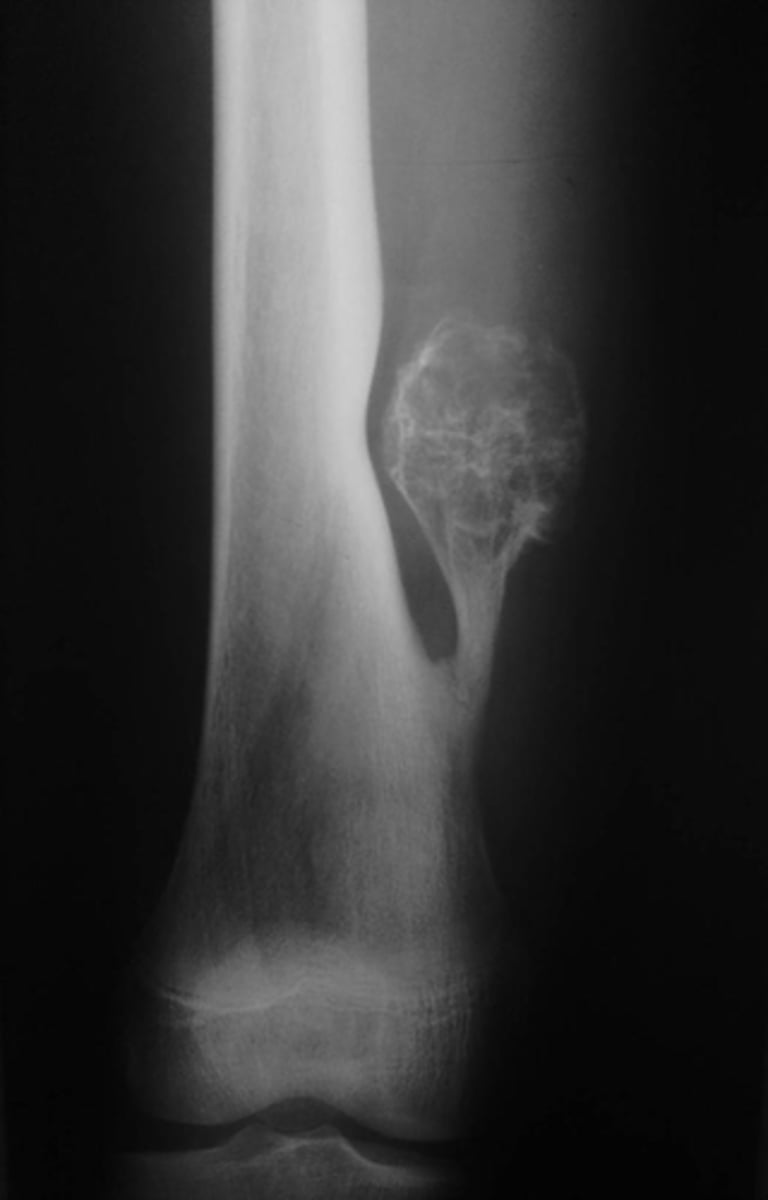

Lateral proximal tibia

Bone

<p>Bone</p>

- Longitudinal: epiphysis/metaphysis (up to joint surface)

- Eccentricity: eccentric

- Transverse: medullary

Location

<p>Location</p>

Monostotic

Mono/polyostotic

<p>Mono/polyostotic</p>

New cards

>1 cm

Size

<p>Size</p>

- Lytic

- Geographic

- Short zone of transition

Behavior

<p>Behavior</p>

- Cortical thinning

- Cortical expansion

Cortex

<p>Cortex</p>

Joint surface involved

Joint involvement

<p>Joint involvement</p>

Giant cell tumor

Most likely diagnosis?

<p>Most likely diagnosis?</p>

Refer to orthopedist or oncologist

Next step?

<p>Next step?</p>

Could be aggressive (20%)

Concerns/complications?

<p>Concerns/complications?</p>